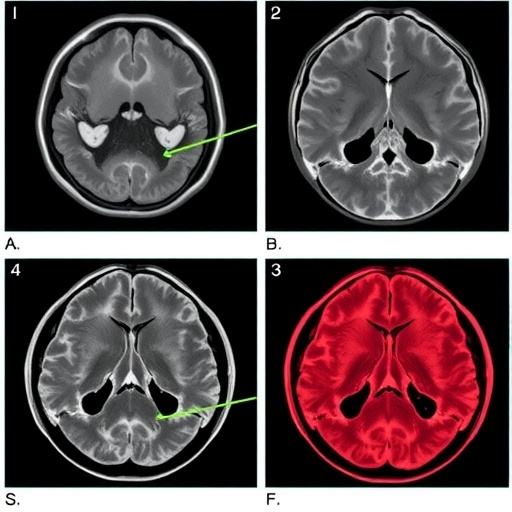

Craniopharyngiomas, benign but locally aggressive tumors located near the pituitary gland, pose substantial surgical challenges due to their proximity to critical neurovascular structures. Their high recurrence rates require many patients to undergo second surgeries, yet there remains no consensus regarding whether transcranial surgery (TCS) or EES offers better outcomes for recurrent tumors. This ambiguity spurred Wu et al. to undertake a methodical comparison to clarify surgical efficacy and safety in these reoperations.

The study further elucidates that the endoscopic transnasal approach, once considered experimental by some, is now safe and effective for removing recurrent craniopharyngioma, offering a less invasive route with improved visual and endocrine outcomes. Nevertheless, surgeons must remain vigilant to mitigate the higher CSF leak rates associated with EES through advanced reconstructive strategies and rigorous intraoperative techniques.